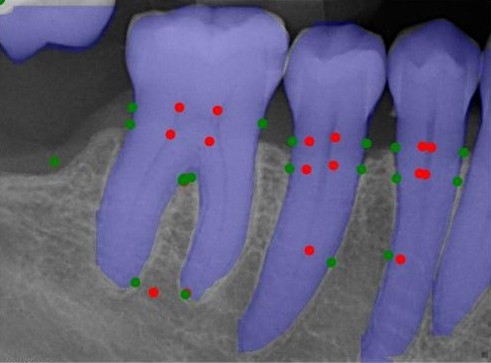

Analysing the validation set, in Figure 8, qualitatively shows that raw predictions rarely coincide with anatomically correct locations, often being detected within the tooth interior or entirely outside its boundary. Post-processing substantially improves localisation in most cases, shifting keypoints towards plausible mesial and distal edges, as shown in Figure 8(a) and 8(d). However, this refinement is heavily dependent on the quality of the raw detections. When predictions are excessively noisy, post-processing can amplify errors, relocating keypoints to implausible locations such as the crown or furcation apex, as seen in Figure 8(g) and Figure 8(h). This further explains the observed quantitative increase for prck0.05prck^{0.05}, but declination at more lenient thresholds, since small adjustments improve low-tolerance metrics, yet fail to increase high-tolerance thresholds.

Refer to caption

(a) Image 120 DeepPose

(b) Image 120 HRNet

(c) Image 120 RTMPose

(d) Image 120 YOLOv8

(e) Image 171 DeepPose

(f) Image 171 HRNet

(g) Image 171 RTMPose

(h) Image 171 YOLOv8

Figure 8: Six validation images with overlay keypoint results, where red points are the raw keypoint predictions and green points are the post-processed keypoints.

Further analysis of post-processing PRCKPRCK metrics at a range of thresholds in Figure 9, all models except HRNet show slightly reduced 0.50.5-0.20.2 threshold performance for post-processed keypoints compared to no post-processing. However, post-processed and non-post-processed performance inverts between a threshold of 0.20.2-0.10.1.